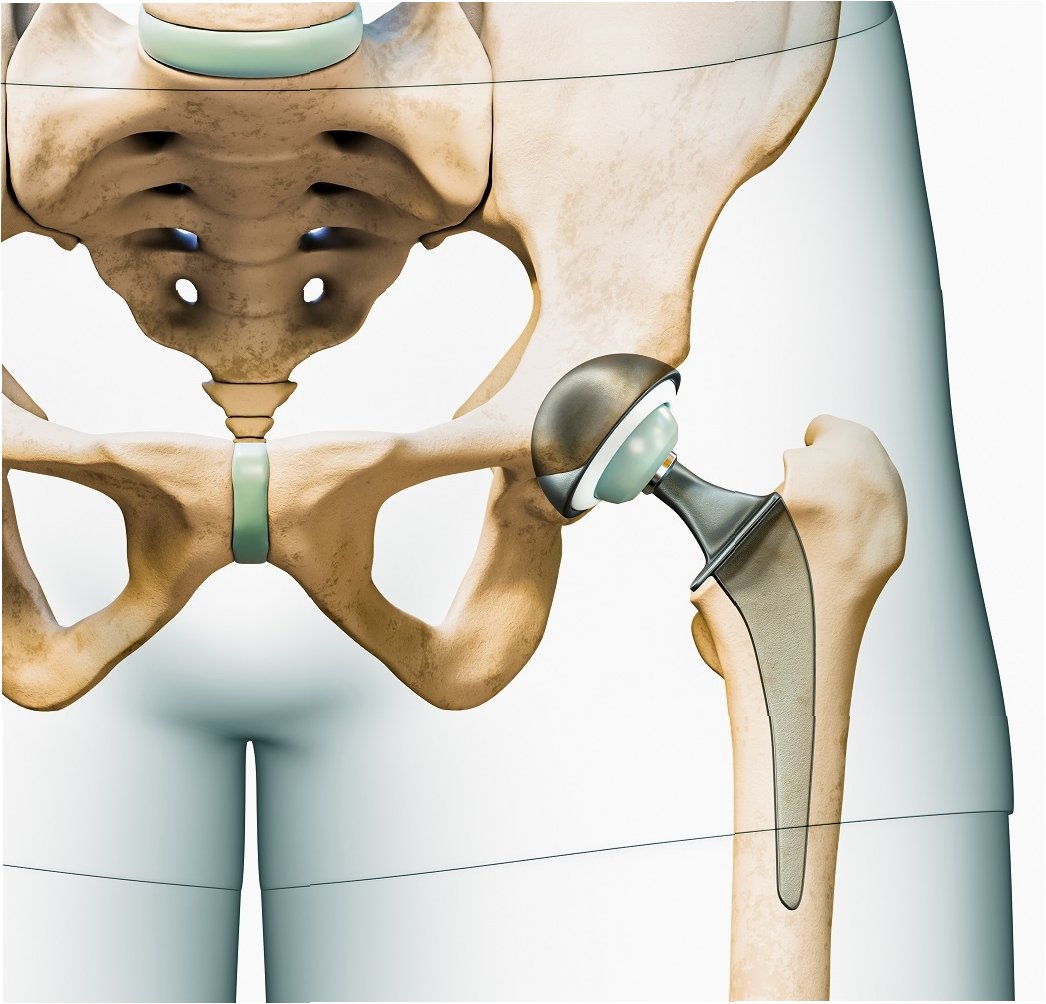

관절은 우리 몸의 움직임을 가능하게 하는 중요한 부분입니다. 하지만 관절 연골이 손상되거나 닳아 없어지면 극심한 통증과 함께 일상생활에 큰 불편함을 겪게 됩니다. 이러한 경우, 인공관절수술은 삶의 질을 향상시키는 효과적인 치료 방법이 될 수 있습니다. 인공관절수술은 손상된 관절을 인공관절로 대체하여 통증을 완화하고 관절의 기능을 회복시키는 것을 목표로 합니다. 수술 후에는 보다 자유롭고 활동적인 생활을 누릴 수 있으며, 긍정적인 심리적 변화도 기대할 수 있습니다. 인공관절수술은 단순히 통증을 없애는 것을 넘어, 환자가 건강하고 행복한 삶을 되찾도록 돕는 중요한 과정입니다.

인공관절수술은 일반적으로 손상된 관절 부위를 절개하고, 손상된 뼈와 연골을 제거한 후 인공관절을 삽입하는 방식으로 진행됩니다. 수술 시간은 관절 부위, 수술 방법, 환자의 상태에 따라 다르지만, 대개 1~3시간 정도 소요됩니다. 수술 후에는 통증 관리와 함께 조기 재활 운동을 시작하여 관절의 기능 회복을 돕습니다. 초기에는 보행 보조기구(목발, 보행기 등)를 사용하며, 점차적으로 사용 빈도를 줄여나갑니다. 재활 운동은 관절의 가동 범위를 늘리고 근력을 강화하여 일상생활 복귀를 돕는 데 매우 중요합니다. 회복 기간은 개인의 상태, 수술 방법, 재활 노력에 따라 다르지만, 일반적으로 수술 후 3~6개월 이내에 일상생활로의 복귀를 목표로 합니다. 꾸준한 재활과 관리를 통해 건강한 관절 기능을 회복하고 오랫동안 유지할 수 있습니다.